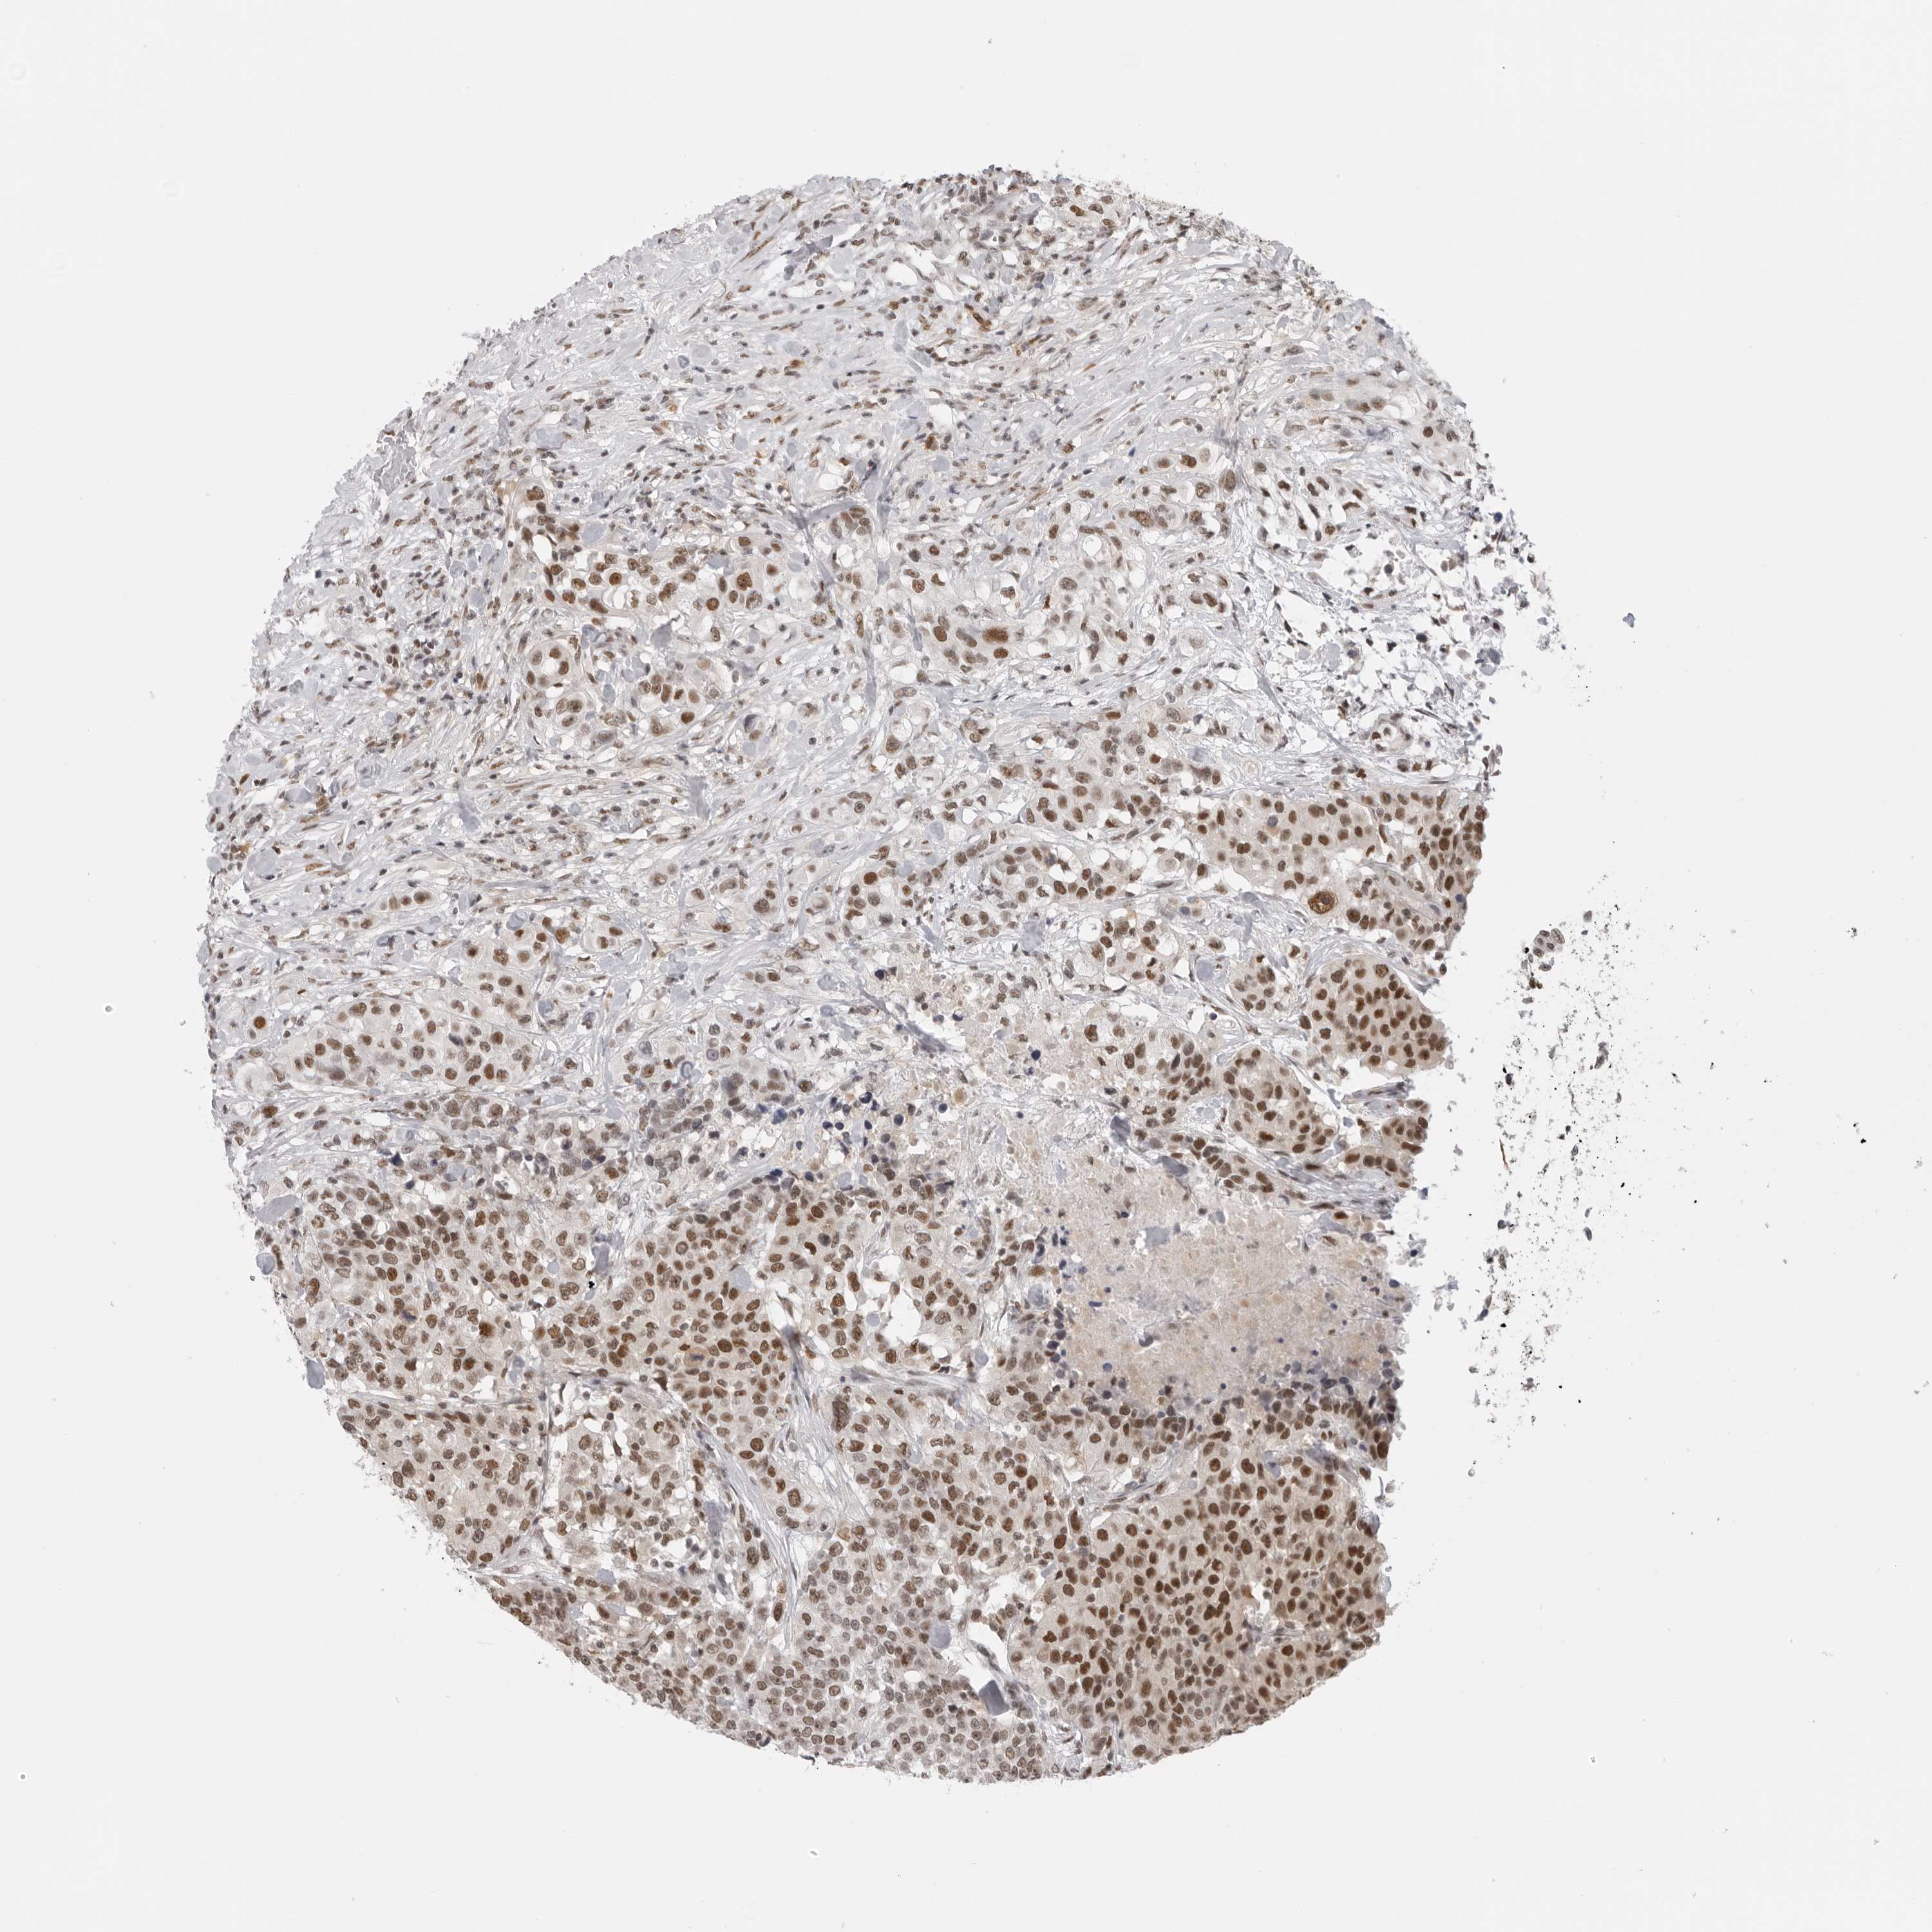

UROTHELIAL CANCER - Protein expressioni

A mouse-over function shows sample information and annotation data. Click on an image to view it in a full screen mode. Samples can be filtered based on level of antibody staining by selecting one or several of the following categories: high, medium, low and not detected. The assay and annotation is described here.

Note that samples used for immunohistochemistry by the Human Protein Atlas do not correspond to samples in the TCGA dataset.

Antibody stainingi

Antibody staining in the annotated cell types in the current human tissue is reported as not detected, low, medium, or high, based on conventional immunohistochemistry profiling in selected tissues. This score is based on the combination of the staining intensity and fraction of stained cells.

Each image is clickable and will lead to virtual microscopy that enables deeper exploration of all samples and also displays staining intensity scores, fraction scores and subcellular localization as well as patient and tissue information for each sample.

Antibody HPA026306

Antibody HPA026309

Antibody CAB016538

Staining

High

Medium

Low

Not detected

Intensity

Strong

Moderate

Weak

Negative

Quantity

>75%

75%-25%

<25%

None

Location

Nuclear

Cytoplasmic/membranous

Cytoplasmic/membranous,nuclear

Urothelial carcinoma, Low grade

Urothelial carcinoma, High grade